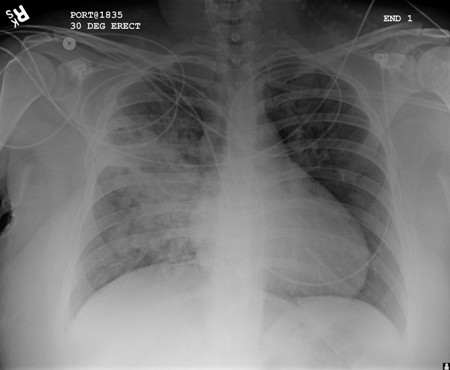

A. Portable upright chest x-ray before aspiration; B. Chest x-ray 1 hour after aspiration, showing bilateral diffuse alveolar infiltrates, worse at the bases on the right side

From the personal collection of Dr S. Murgu and Dr H. Colt, University of California at Irvine Medical Center